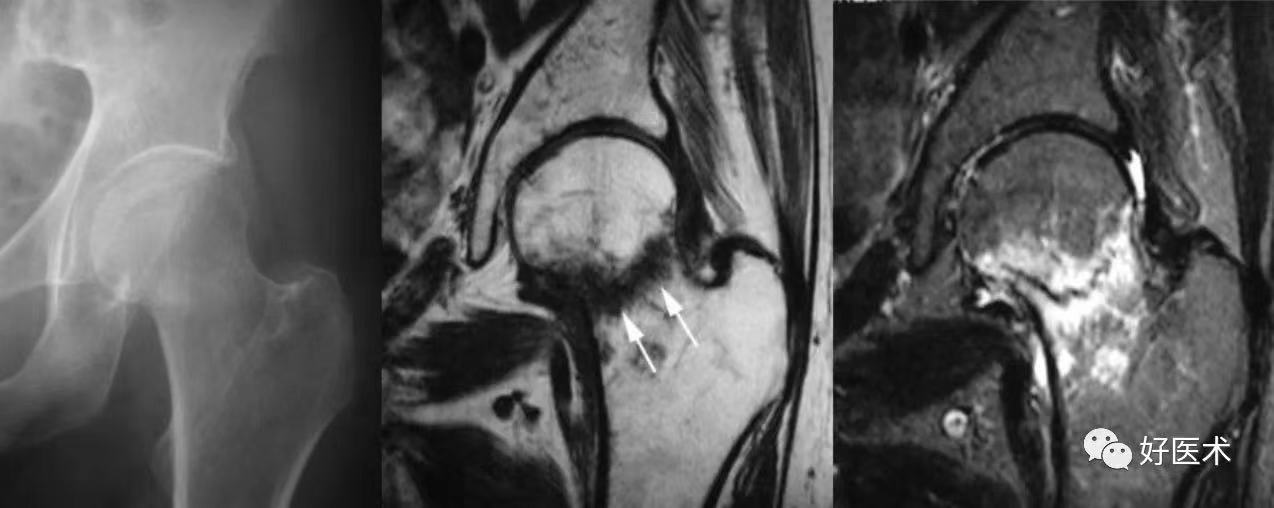

髋关节后脱位:常见于青壮年,有强大暴力损伤史;弹性固定于屈髋、屈膝、内收、内旋位,在臀后可扪及脱出的股骨头;X线片可鉴别。